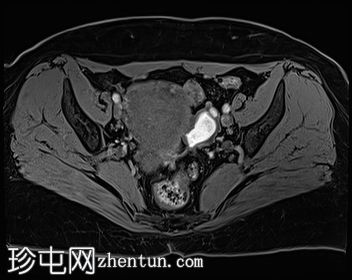

冠状位

T1加权像

左侧卵巢可见数个小囊肿,在T1加权像上呈高信号,在T2加权像上呈低信号(T2阴影),T1脂肪抑制序列未见信号下降,提示其为血液降解产物。最大的囊肿轴位大小约为3.1×1.7 cm,轻度压迫卵巢实质。

右侧卵巢可见黄体囊肿。未见实性肿块。

盆腔少量游离液体。

少数左侧卵巢囊肿伴有上述出血信号,可能代表子宫内膜异位囊肿,因为多发性和双侧性更倾向于子宫内膜异位囊肿而非出血性囊肿。